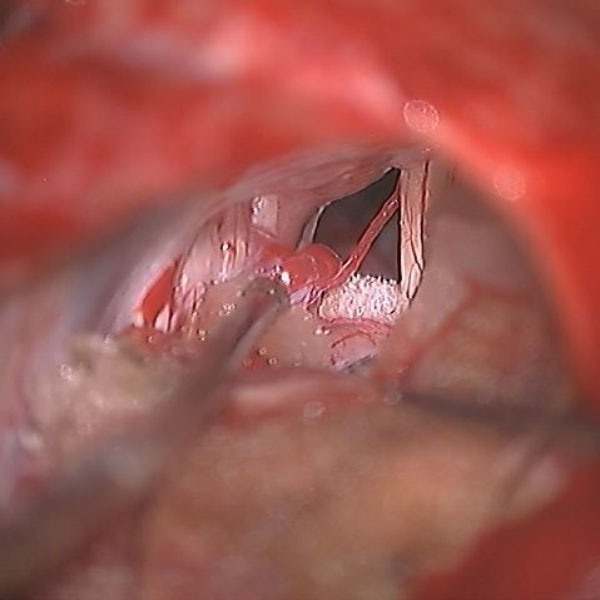

手術中

処置後